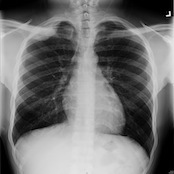

Researchers have developed a breath test that has the ability to detect lung cancer and differentiate between malignant or benign lesions. Though the technology is still in the early stages of development, it is a promising step in the improved detection of lung cancer without invasive tests or CT imaging.

New technology to detect lung cancer early is desperately needed, and this new breath test seems to fit the bill. The test uses mass spectrometry and a silicon microprocessor to detect the presence of organic compounds that are exhaled by patients with lung malignancies. The test found an elevation of three or four of these organic compounds had a 95 percent predictive rate for malignancy. The absence of these elevated levels correctly predicted a benign mass in 80 percent of patients.

Breath test technology would be a great way to acknowledge those patients in the early stages of lung cancer. Patients with high risk factors could be identified and take the test before the disease spreads to other parts of the body — with a deadly cancer like this, the earlier a malignancy can be detected, the better the chance of successful treatment.